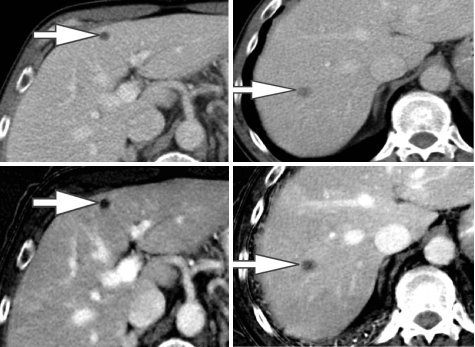

Evaluation of little liver lesions on typical CT is typically a diagnostic plight. Sub centimeter lesions area unit typically very little to characterize, leading to the necessity of a lot of investigations with tomography or diagnostic test. Cysts are typically differentiated from metastases (small hypodense masses) on iodine pictures in Associate in the extremely DECT scan as a result of a metastasis will uptake iodine whereas a cyst will not (Figure 4) [20].

Figure 4. A 65-year-old man with a history of the malignant neoplastic disease. Contrast-enhanced Porto venous section single energy CT pictures show tow small rounded hypodense lesions in internal organ segments IV (arrow in A) and VII (arrow in B), that are really similar in look. Iodine material decomposition pictures reveal the varied nature of the tow lesions. the phase IV clinical trials lesion demonstrates no uptake of iodine and is so a cyst (arrow in C), whereas the section VII lesion demonstrates iodine uptake (arrow in D) and is so a metastasis.